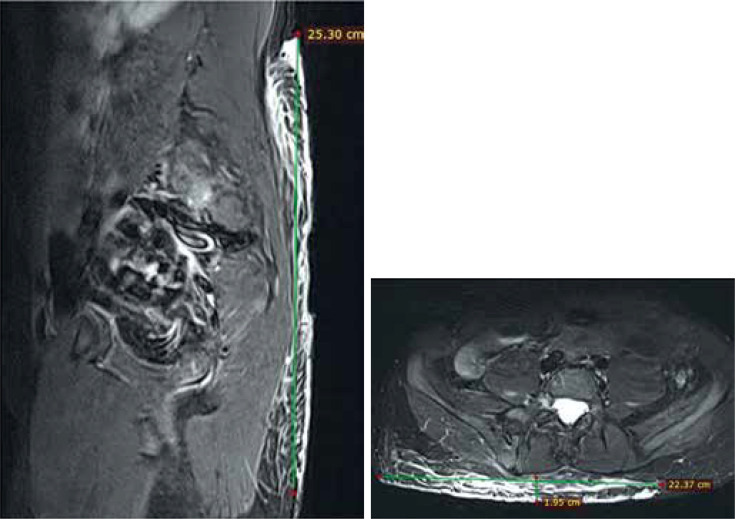

1型神经纤维瘤病(NF1)是一种遗传决定的疾病,具有复杂的临床症状,包括许多系统和器官的疾病,易导致各种癌症的发展。大约10-30%的NF1患者发展为丛状神经纤维瘤(PN),这是一种沿神经生长的非恶性肿瘤,易于浸润神经和神经丛,并可能生长到内脏器官、椎管、中耳、骨骼变形和身体的各个部位。核磁共振成像(MRI)作为一种基线筛查工具,在PN过程中的个体管理中起着关键作用,用于监测(已知PN个体),评估治疗反应,以及术前评估手术计划。本文提出的实用建议旨在规范NF1过程中PN的MRI检查方案,以便在波兰的临床项目中进行治疗。该方案包括体积MRI检查,成像时间表,目标变化的确定,测量病变体积的技术,以及怀疑的恶性转化,旨在成为这些患者每次检查中必须包含的最小MRI序列和视图集。

Neurofibromatosis type 1 (NF1) is a genetically determined disorder with a complex clinical picture, including disorders of many systems and organs, that predisposes to the development of various cancers. Approximately 10-30% of patients with NF1 develop plexiform neurofibromas (PN), non-malignant tumours growing along the nerves, tending to infiltrate nerves and nerve plexuses, and may grow into internal organs, the spinal canal, and middle ear, deforming bones and various regions of the body. Magnetic resonance imaging (MRI) plays a key role in the management of individuals during the course of PN, as a screening tool at baseline, for surveillance (in individuals with known PN), to evaluate treatment response, and for preoperative assessment for surgical planning. The practical recommendations presented in this article aim to standardise the protocol for MRI examination of PN in the course of NF1 for the purpose of treatment in a clinical program in Poland. The protocol, covering volumetric MRI examination, imaging schedule, determination of the target change, the technique for measuring the volume of lesions, and suspected malignant transformation, is intended to be the minimum set of MRI sequences and views that must be included in every examination of these patients.